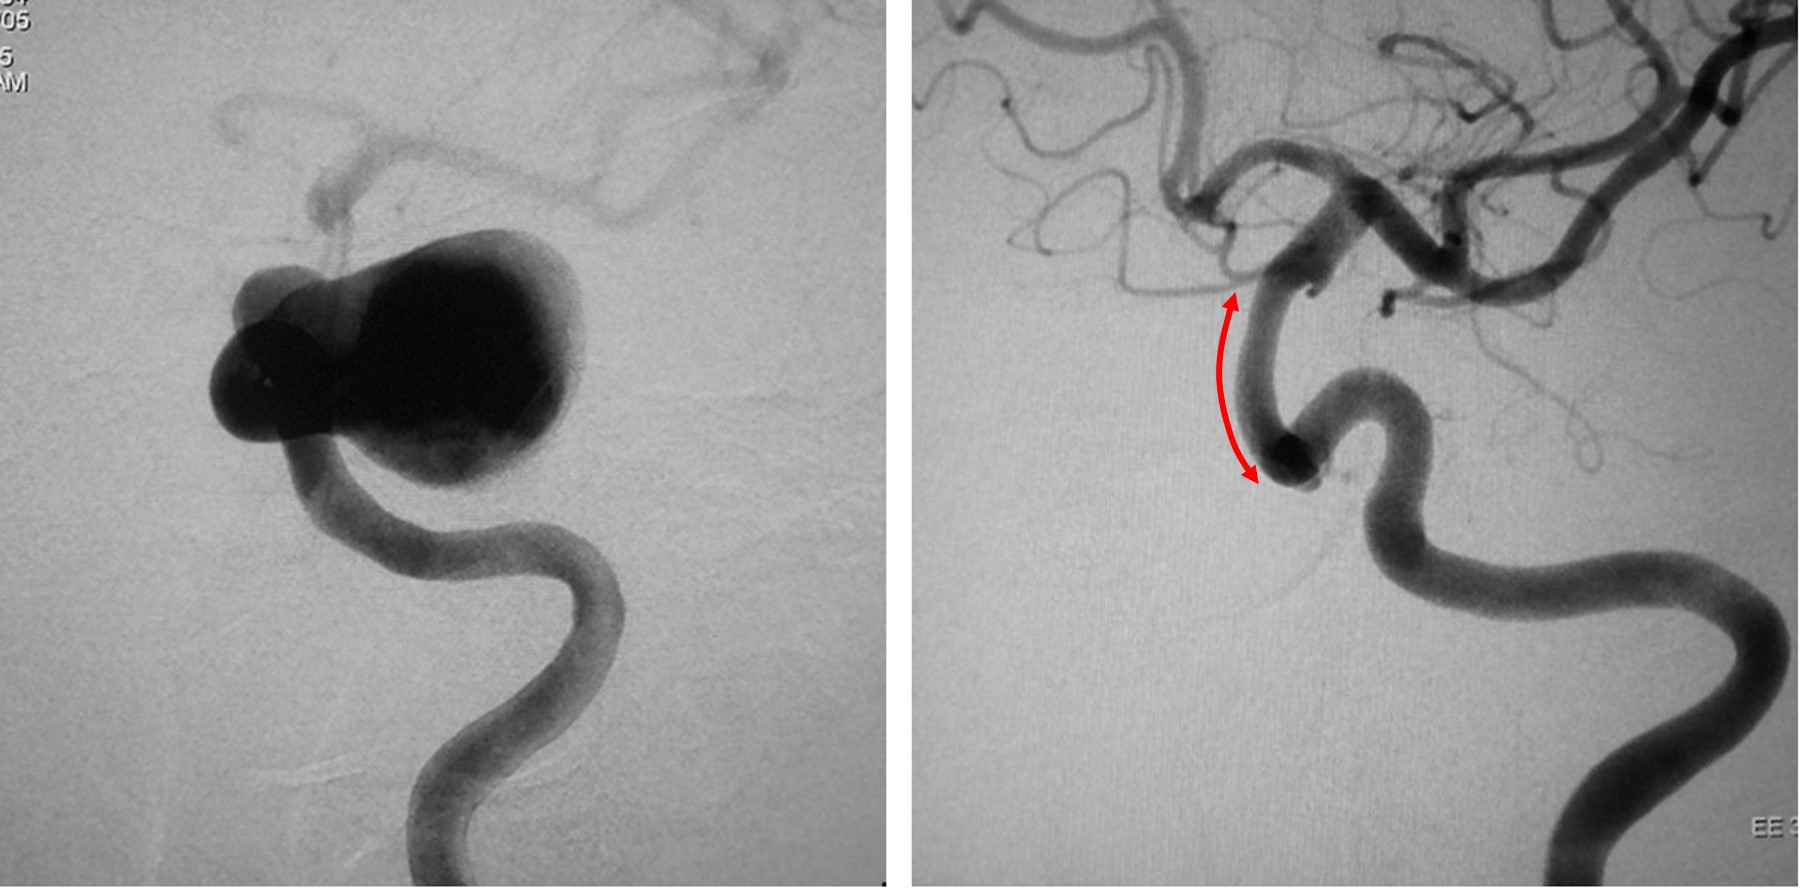

図:フローダイバーター治療前(左)と治療から半年後(右)の画像。

矢印の範囲の血管にフローダイバーターが留置されている。